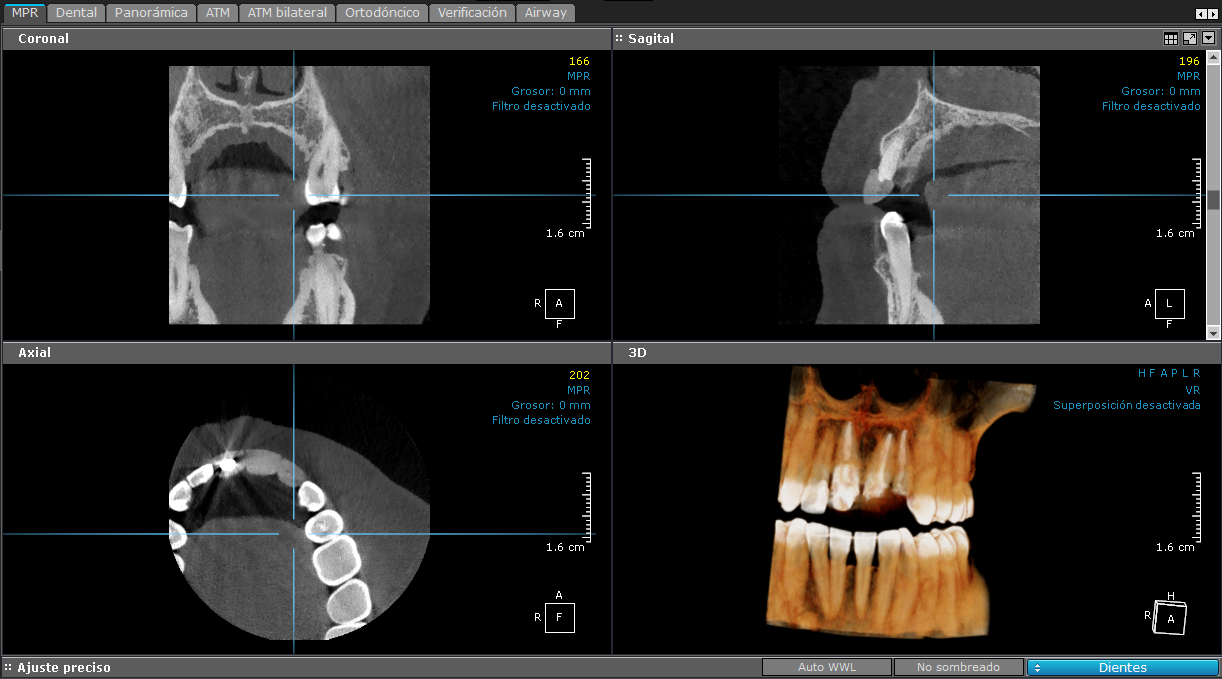

3D - Cara Completa

Cara completa

Muestra la totalidad de la estructura facial y mandibular (arcadas superior e inferior, huesos maxilares, mandíbula y estructuras de soporte). Está particularmente indicada para la valoración del número y la posición de los dientes, por lo que son muy útiles para la planificación de una ortodoncia e implantes.